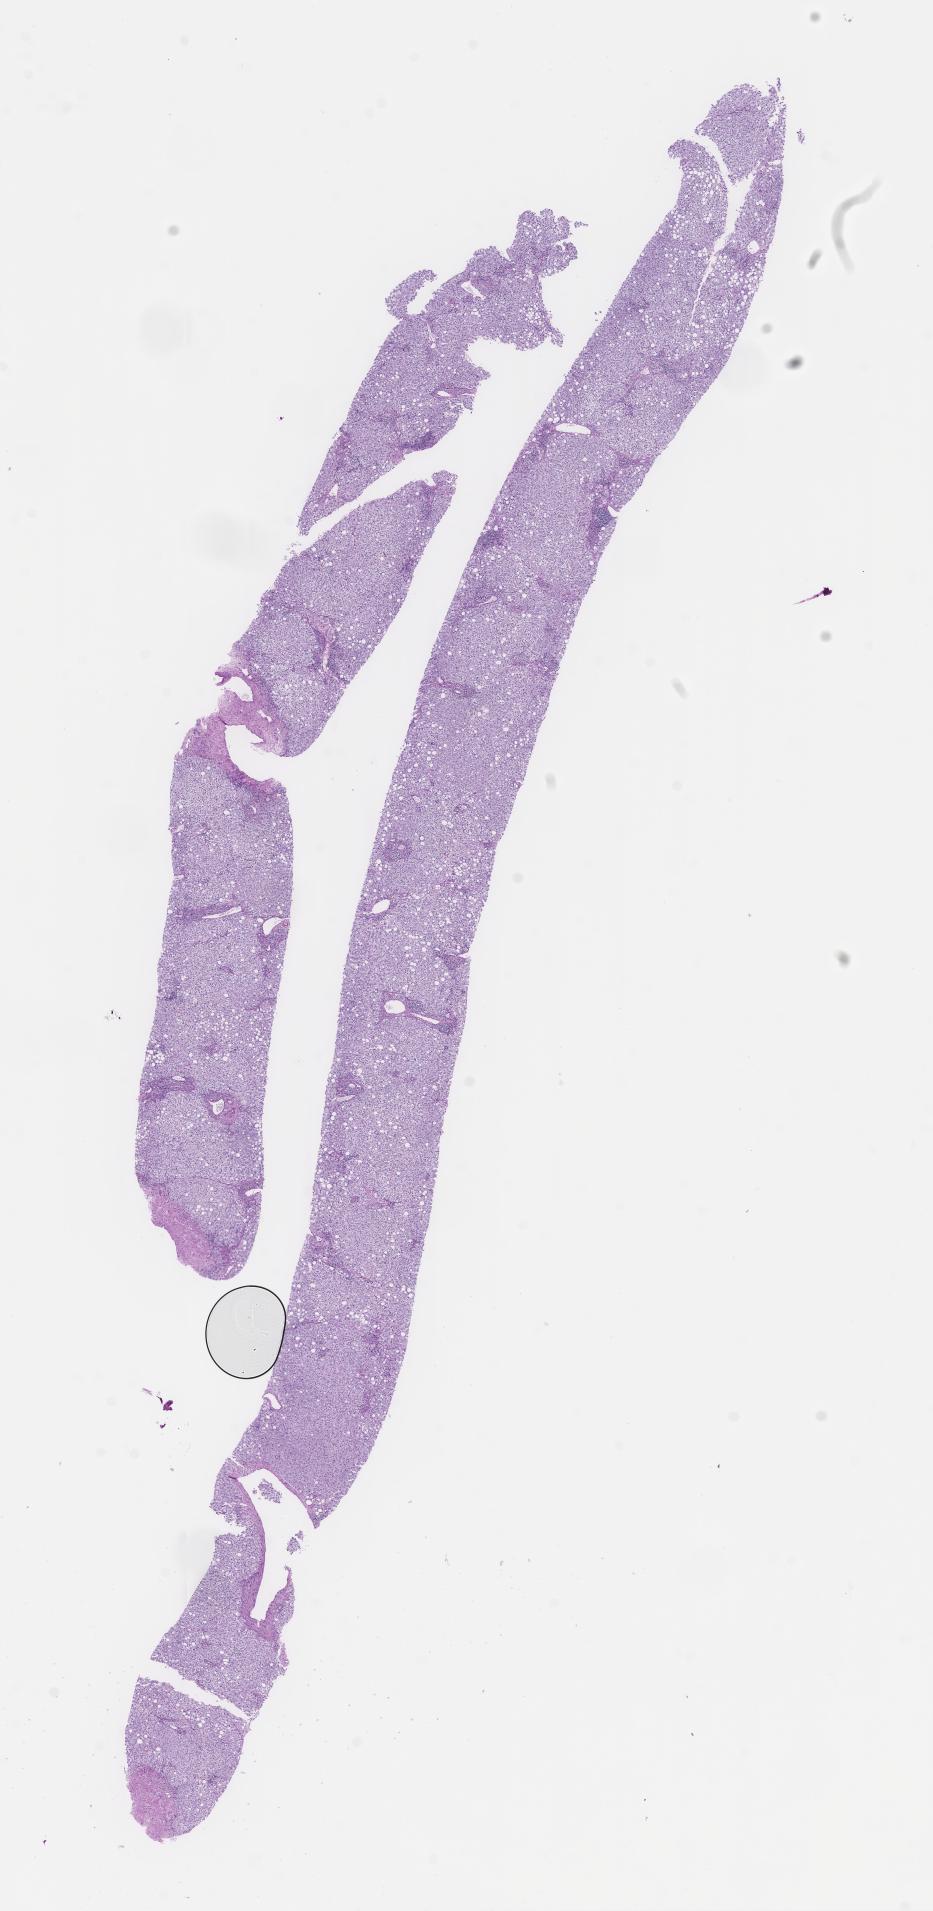

This dataset contains anonymised whole slide images (WSIs) of human liver received during routine clinical practice, comprising a variety of benign and malignant diagnoses. This dataset includes biopsies comprising a mixture of non-targeted/medical and tumour (primary or metastatic) All cases include a H&E stain along with any additional histochemical or immunohistochemical stains where available.

Perls (Iron) Immuno Spare Periodic Acid-Schiff Immunohistochemical (IHC) staining for CD3 Synaptophysin Immunohistochemical (IHC) staining for CD138 Hepatitis B surface antigen Chromogranin A Hematoxylin and Eosin Glutamine Synthetase Immunohistochemical (IHC) staining for Ki-67 Shikata Orcein stain Elastic Van Gieson Cytokeratin Associated Marker 5.2 Rhodanine Immunohistochemical (IHC) staining for caudal-related homeobox gene 2 Reticulin Immunohistochemical (IHC) staining for CD20 CytoKeratin 7 Immunohistochemical (IHC) staining for CD34 Congo Red Periodic Acid-Schiff with Diastase Van Gieson |